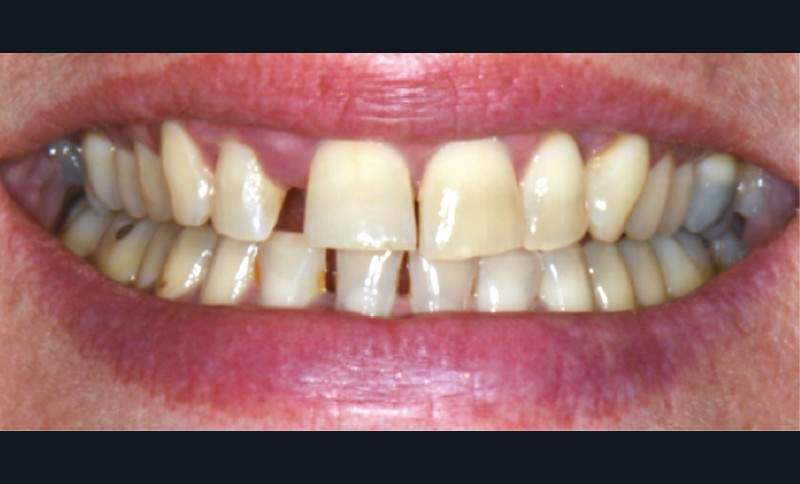

Formes cliniques

La MDP est dépendante de l’axe des forces appliquées à la dent. Ces forces peuvent ainsi conduire à des déplacements horizontaux, des versions (basculement par rotation) et/ou des égressions/extrusions (déplacement vertical seul, souvent retrouvé lors de la perte de dent antagoniste).

Des combinaisons de mouvements sont le plus souvent retrouvées, notamment lors de la perte du calage postérieur : déplacement horizontal et vertical, migration « en éventail ».